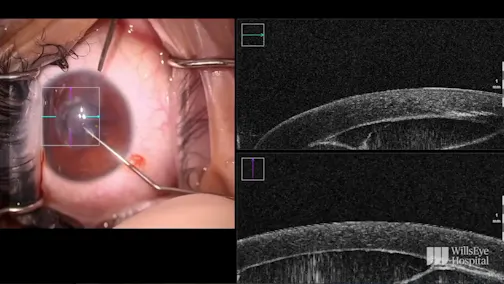

John F. Doane, MD, FACS